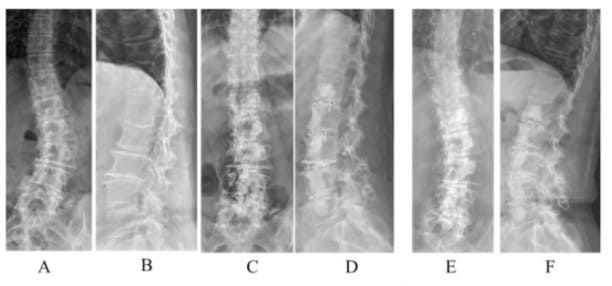

Figure 3: A 75-year-old female with degenerative scoliosis 38’ and lumbar lordosis 14’ (A, B) underwent OIBC. Immediate postoperative scoliosis was 6’ and lumbar lordosis was 28’ (C, D). Five years later, scoliosis was 10’ and lumbar lordosis was 27’ (E, F).

Figure 9: A 60-year-old female with degenerative scoliosis (A, B) underwent L2/S1 OIBC. One-month follow-up showed good correction (C, D). The patient remained symptom-free at the final follow-up after six years. (E, F).

Figure 10: A 79-year-old female with degenerative scoliosis 40° and lumbar kyphosis 34° (A, B) underwent PIBC. Immediate postoperative scoliosis was 5° and lumbar lordosis was 13° (C, D). Eighteen months later, the scoliosis was 3° and lumbar lordosis was 5° (E, F). Asymptomatic cement leakage was observed on the ventral side of the L1 vertebral body.

Figure 11: A 75-year-old female with degenerative scoliosis of 43° and lumbar lordosis of 36° (A, B) underwent L2/4 OIBC. Immediate postoperative scoliosis was 5° and lumbar lordosis was 48° (C, D). She underwent L1/2 PIBC 41 days later. (E, F), which was wellmaintained at the final follow-up at one year (G, H).